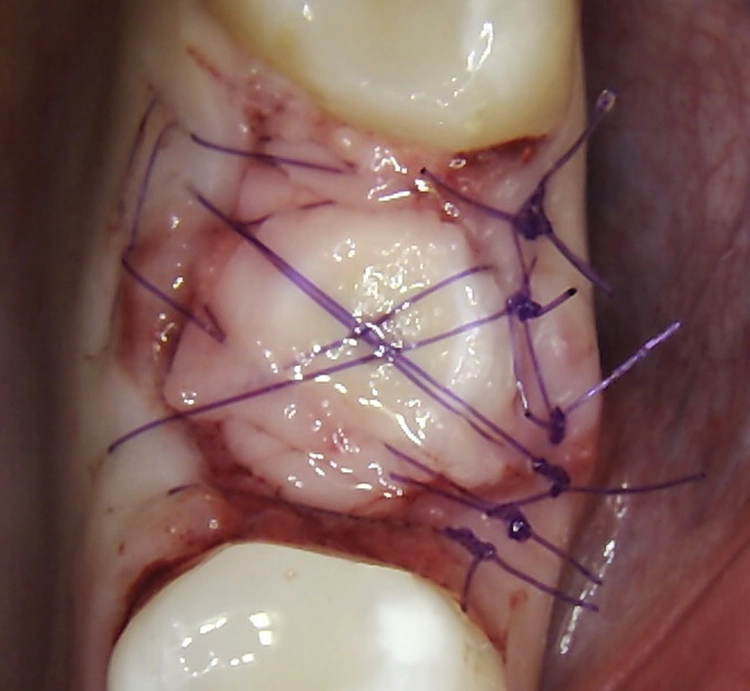

Die Augmentation des Alveolarkamms richtete sich nach der Größe des Defekts. Der Kollagenblock (Condress 5 x 5 cm, Smith & Nephew) wurde auf die erforderliche Größe zugeschnitten und am Alveolarkamm sowie um das Implantat herum verdichtet. Zur Stabilisierung der A-PRF-Matrizen und des Kollagenblocks sowie zur Repositionierung des Lappens wurde eine nicht resorbierbare monofile Naht (Atramat® 5-0, Mednaht) verwendet. Vor der prothetischen Belastung mussten die Implantate 4–8 Wochen einheilen.

Bei dem balkonförmigen Implantat blieben die Alveolarkämme und der Kronenansatz erhalten (Abb. 4c und d). Der Spalt zwischen dem Implantat und der bukkalen Lamelle wurde mit A-PRF und einem Kollagenblock aufgefüllt, so dass keine zusätzliche Knochenaugmentation erforderlich war. Zusätzlich wurden PRF-Matrizen um, über, unter und neben dem Implantat im Knochen-Implantat-Raum positioniert (Abb. 1 bis 4b). Außerdem kam eine optionale Einheilscheibe (6 x 8 mm) zum Einsatz, um das Kollagen und die PRF zu sichern (Abb. 3b). Die Implantate zeigten bei einem Drehmoment von 35 Ncm Stabilität, welche mit dem Periotest-Gerät von Medizintechnik Gulden getestet wurde. Die Werte des Implantatstabilitätstests, die im Bereich von –8 bis 0 lagen, wurden als ideal für die Belastung angesehen (Tab. 3).

Abb. 2: Repräsentativer Fall von ABH Grad B Septus Typ II. a) Ansichten vor der Installation. Röntgenaufnahme der periapikalen Läsion an einem wurzelkanalbehandelten Molaren und klinische Ansicht der Typ-II-Socket nach der Extraktion. b) Die Ansichten nach der Installation zeigen das Implantat innerhalb des interradikulären Septums und das über dem Implantat platzierte A-PRF. c) Nachuntersuchungen nach 10 Tagen bzw. 2,1 Monaten. Die Röntgenaufnahme zeigt die Knochenbildung zwischen der Sinusmembran und dem apikalen Teil des Implantats. d) Jüngste Nachuntersuchung nach Einsetzen der Prothese.

Abb. 3: Repräsentativer Fall von Grad A Typ I. a) Präoperative Ansicht. Röntgenbild der periapikalen Läsion an einem wurzelkanalbehandelten Molaren. Die Höhe des Alveolarknochens zeigt Grad A an. b) Klinische und radiographische Ansicht der Implantatinsertion unter Verwendung einer Einheilscheibe mit großem Durchmesser (6×8 mm). A-PRF wurde um das Implantat und unter der Scheibe platziert. c) Nachuntersuchung nach 5,9 Monaten vor und nach der Zementierung und Aufbereitung. d) Jüngste Nachuntersuchung nach Einsetzen der Prothese